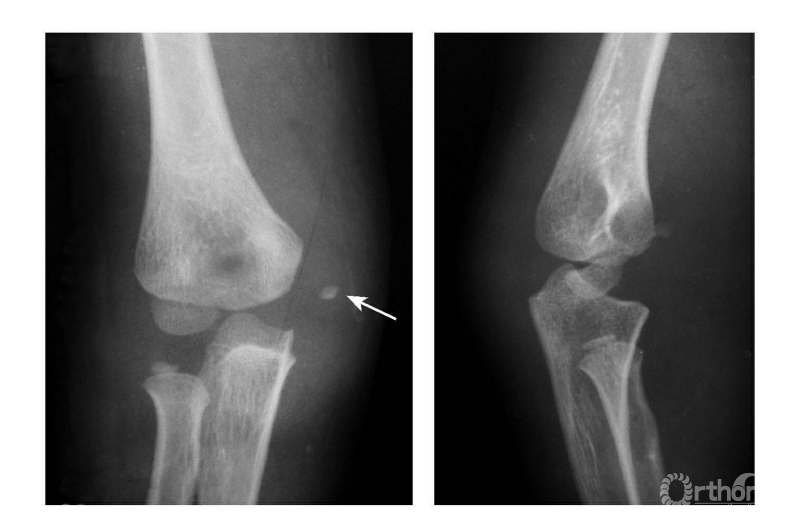

Ⅱ度损伤:

例1:内上髁骨骺分离并带一模糊的骨皮质,并向外侧旋转,而达关节水平(图4)。

图4